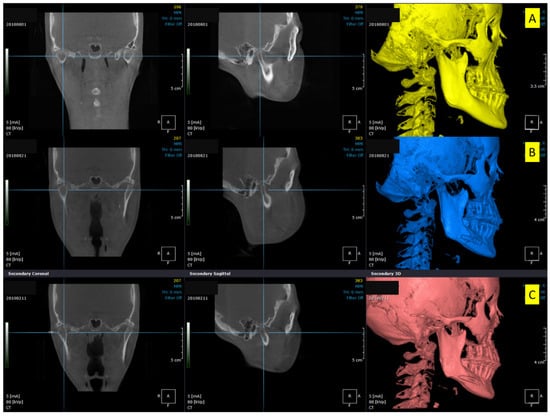

Figure 3.

Three-dimensional cone-beam computed tomography scans showing the changes in condylar positions in Patient no. 2. (A) Pre-surgical, (B) Post-surgical, (C) Five months after screw removal. Increased temporomandibular joint space is seen in (B). After screw removal, the joint space decreased and was restored to the pre-surgical state.